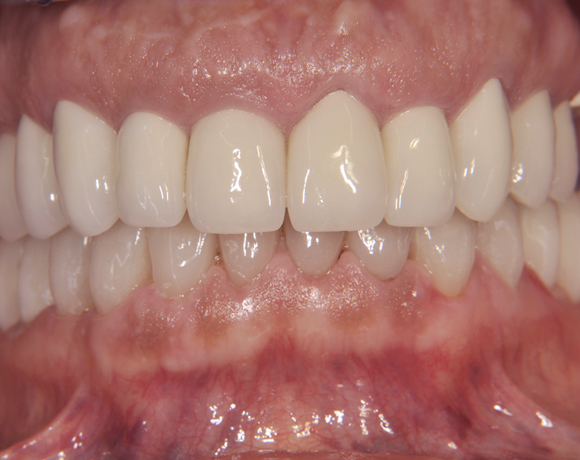

Der vorliegende Patientenfall zeigt eine komplette Neuversorgung der vorhandenen Metallkeramikkronen mit vollkeramischen Restaurationen. Zusätzlich wurde im Oberkiefer die Zahnreihe mit zwei Implantaten, für die fehlenden Molaren, ergänzt. Da keine ausreichende Knochenhöhe vorhanden war wurde ein interner Sinuslift geplant.